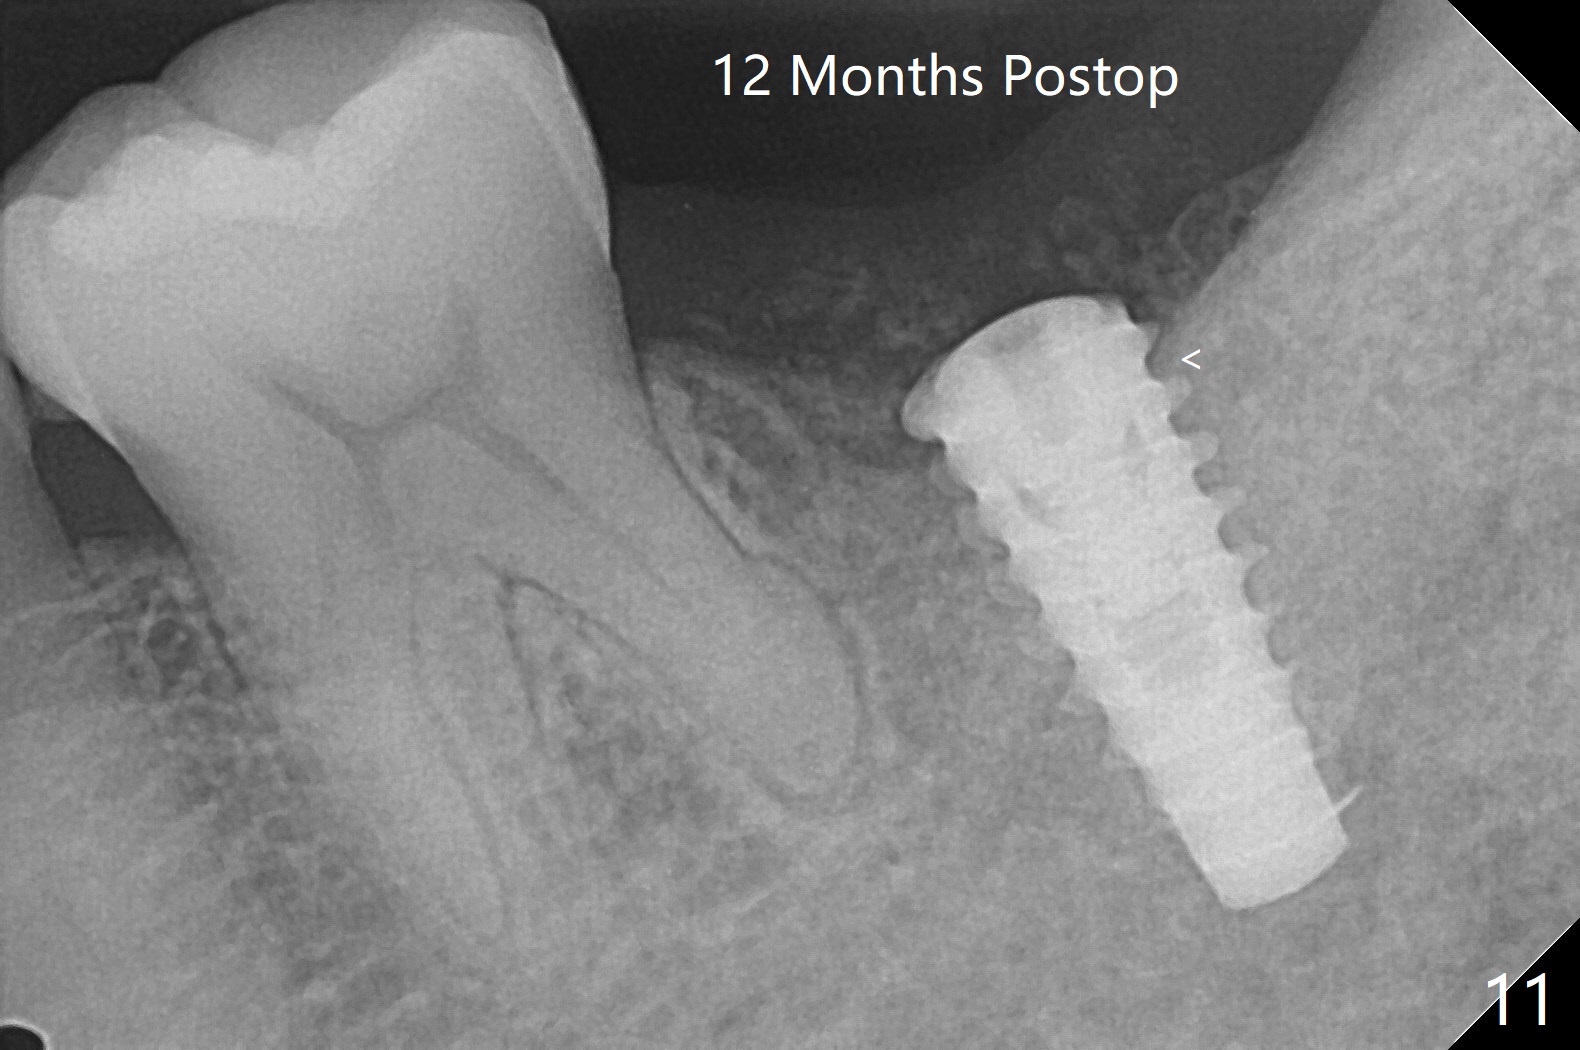

After placement of a 5x11 mm implant and cover screw at #18, allograft mixed with PRF (sticky bone) is placed in the peri-implant space, but it appears that bone density in the apical region (Fig.1 A) is lower than that in the coronal one (C) because of a constriction between the implant and the distal crest (*). Ideally the undercuts (Fig.2 *) of the extraction socket (black area) should be identified. Place bone graft in the undercuts (Fig.3 red circles) after osteotomy (white outlines) and before implant placement! A 4.5x1 mm temporary abutment is placed for an immediate provisional. The 2nd shortcoming of this case is that the implant is placed a little buccal. The papilla mesial to the immediate provisional (Fig.4 P) looks normal 4 days postop (no food impaction is expected when a final restoration is cemented). Additional acrylic (*) was placed to close a buccal gap when the provisional was seated with the temporary abutment. The patient reports loss of a piece of material in 4 days. It must be the additional acrylic, since it is absent 6 weeks postop (Fig.5). The provisional (Fig.5 P) looks wide, probably related to post-extraction gingiva and bone atrophy (Fig.6, 7 *). Bone graft (Fig.6 <) becomes a component of the gingival cuff. The provisional is re-trimmed for better oral hygiene. The gingival cuff is basically healthy 3.5 months postop, although the temporary abutment is loose and the implant is tender to rewinding and winding (Fig.8). The implant seems to remain non-osteointegrated 3.5 months postop (Fig.9). Although the bone density around the implant increases nearly 6 months postop (Fig.10), the implant remains tender when a 5x4(4) mm pair abutment is tightened. The healing abutment is reused. The bone density around the implant increases 11 months postop (Fig.11). Uncover is done with 5.5 mm profile drill. One month post uncover (12 months postop), the implant remains unstable (Fig.12). Prepare sticky bone x1. Make incision for exploration, including retightening the implant after Titanium brush and H2O2 Q-tip rubbing. If needed, a larger and shorter UF implant is a replacement (Fig.13). The implant is removed, cleaned with Titanium brushes and H2O2 in vitro and repositioned 12 months postop (Fig.14: arrow (gaps: post granulation tissue removal)). The gaps are regrafted with sticky bone and covered with PRF membrane and Cytoplast. Although the patient complains of severe pain the first 2-3 postop, the wound is apparently healing 12 days postop. The Cytoplast is exposed asymptomatic 5 weeks postop (Fig.16) and removed (Fig.17). The wound appears to have healed without loss of the bone graft (Fig.18).术后四个月伤口愈合,骨粉几乎没有丢失,有骨小梁形态(图十九:*)。切开,刮匙去骨,有一定硬度,即刻放置修复基台,完全就位(图二十),制备临时牙冠,牙周敷料固定组织瓣(没有缝线)。